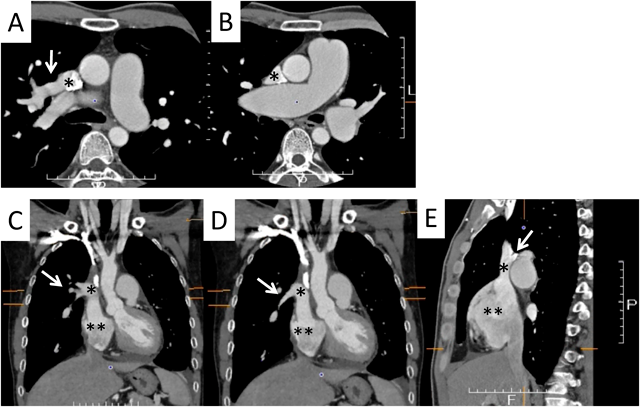

A 42-year-old man was referred to our hospital because of fatigue and exertional dyspnea; he often complained dyspnea when going up stairs. The cause of fatigue and dyspnea had not been detected, although he visited multiple clinics and his chest radiography at medical checkup already showed dilatation of the bilateral pulmonary arteries (Fig. 1A). He was unable to go to work due to his symptoms. On physical examination, his blood pressure and pulse rate were 114/86 mmHg and 78 bpm, respectively. He had a regular rhythm and a respiratory rate of 12 bpm with a percutaneous oxygen saturation of 98% in room air. His second heart sound was accentuated, and no heart murmur audible. A 6-minute walk distance was 390 m. These findings suggested that he was classified into New York Heart Association (NYHA) functional class III. Electrocardiography showed regular sinus rhythm, axis deviation and right ventricular hypertrophy with complete right bundle branch block (Fig. 1B). Echocardiography showed enlargement of the right ventricle and flattening of the interventricular septum. Doppler measurement of tricuspid regurgitation revealed that estimated right ventricular pressure was 103.1 mmHg (Fig. 2A, B). Contrast-enhanced computed tomography illustrated that the right upper and middle pulmonary veins (PVs) drained into the SVC, and that the pulmonary arteries as well as the right ventricle were dilated. Additionally, these anomalous PVs had been shifted upward due to the dilated right pulmonary artery (Fig. 3). During this investigation, the patient suddenly collapsed with low blood pressure, and immediate cardiopulmonary resuscitation was needed. Probably, PAH deteriorated subsequent to injection of contrast media, causing acute volume overload and an increase in pulmonary vascular resistance. Right heart catheterization (RHC) eventually revealed the systemic to pulmonary blood flow ratio (Qp/Qs) 1.4, mean pulmonary arterial pressure (PAP) 91 mmHg, pulmonary capillary wedge pressure 12 mmHg, and pulmonary vascular resistance (PVR) 20.3 WU, respectively (Table 1). Acute vasodilator test using the combination of inhaled oxygen and nitric oxide (iNO) showed PAP and PVR remaining unchanged. PAH related with heredity, drugs and left ventricular dysfunction, respiratory diseases were ruled out after PAH workup. Consequently, we started a combined therapy using PAH-specific drugs. Macitentan (20 mg/day) and tadalafil (10 mg/day) were immediately administered after the RHC. In addition, selexipag was gradually increased from 2 to 10 mg/day at our outpatient clinic. The second RHC took place 6 months after introduction of the PAH drugs, measuring mean PAP 49 mmHg (69/39 mmHg) and PVR 8.6 WU. The Qp/Qs ratio had increased to 2.0 (Table 1). The third RHC was carried out 9 months after initiation of the PAH drugs; mean PAP 45 mmHg (64/30 mmHg), which was similar to the value at the second RHC. Furthermore, PVR markedly improved (down to 2.7 WU), and the Qp/Qs ratio increased (up to 3.2) (Table 1). The patient’s exercise tolerance became better thereafter as his PAH improved. On the other hand, side effects of the PAH drugs, such as diarrhea and headache, gradually resulted in poor medication adherence. As interruption of PAH drugs likely results in progressive PAH, we decided to recommend surgical repair.

Fig. 1 Preoperative chest X-ray (A) and electrocardiogram (B)

CTR, cardio-thoracic ratio.